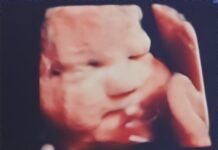

Local mother travels to Texas to seek care for unborn baby

CULLMAN, Ala. – Cullman resident Holliann Letson was enjoying a typical pregnancy with her second daughter, Evelyn. At her 18-week anatomy scan – the...